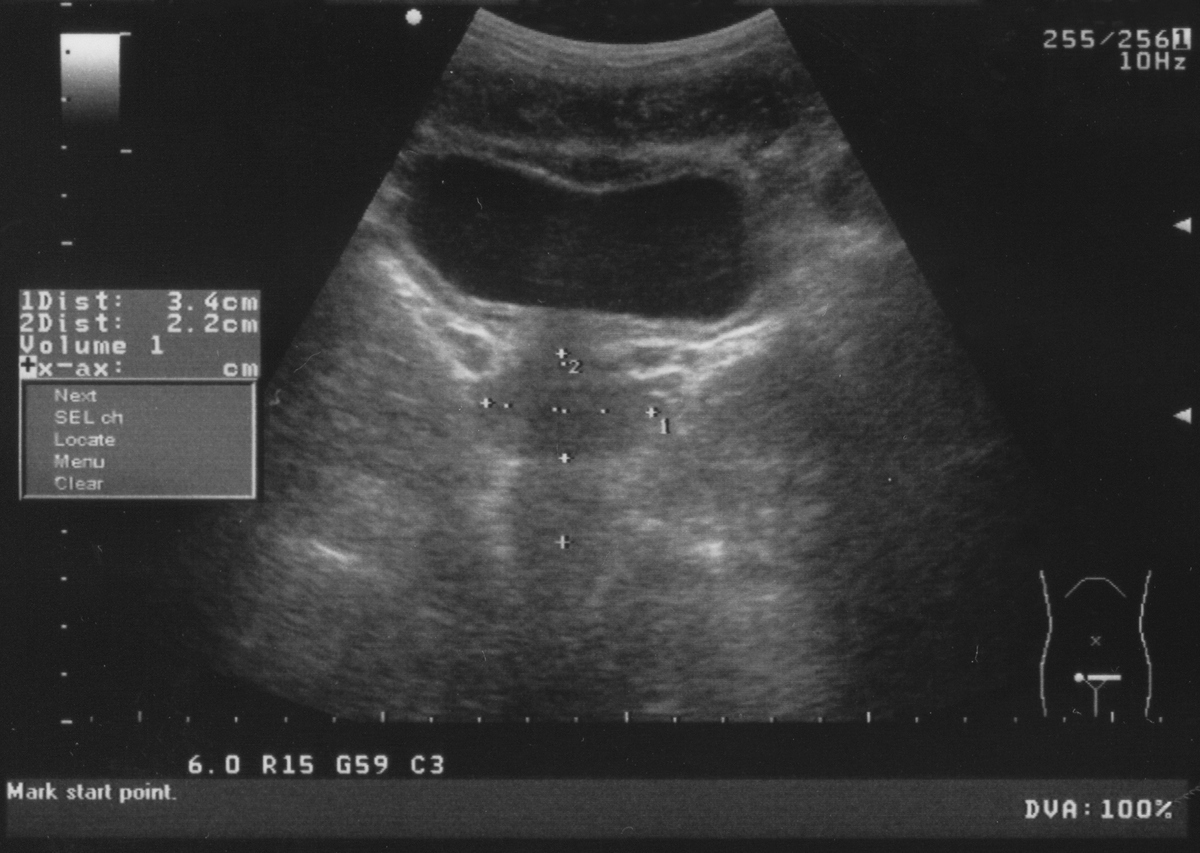

Ο ολοκληρωμένος προσυμπτωματικός έλεγχος περιλαμβάνει αιματολογικό έλεγχο του PSA (Prostate-Specific Antigen), το Ειδικό Προστατικό Αντιγόνο που ανιχνεύεται στο αίμα, και τη δακτυλική εξέταση, και πρέπει να γίνεται κάθε χρόνο.